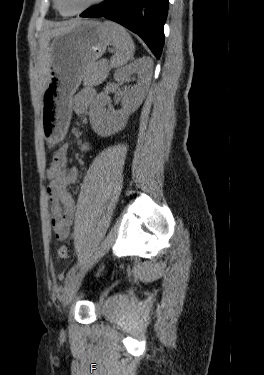

Методика КТ позволяет оценить анатомическое строение почек, надпочечников, состояние мочеточников и мочевого пузыря, кроме того, дает возможность визуализировать сосудистую систему и регионарные лимфатические узлы.

Сканирование применяется для выявления воспалительных заболеваний почек, чашечно-лоханочной системы, мочеточников и мочевого пузыря, также позволяет обнаружить конкременты на фоне мочекаменной болезни, диагностировать доброкачественные и злокачественные новообразования, точно классифицировать кистозные образования по системе Bosniak, что особенно важно для урологов и нефрологов, а также определить степень поражения регионарных лимфатических узлов. Кроме того, КТ используется для диагностики травматических повреждений органов мочевыделения, аномалий развития почечно-лоханочной системы, дает максимальную информацию для хирурга при планировании оперативного вмешательства.

Что показывает КТ почек, мочеточников, мочевого пузыря

- опущение почек;

- аномалии развития почек, мочетоников

- доброкачественные и злокачественные новообразования;

- камни (конкременты);

- уретероцеле

- сосудистую патологию (сосудисто-мочеточниковый конфликт, инфаркт почки);

- последствия оперативных вмешательств;

- увеличение лимфоузлов в брюшной полости, забрюшинном пространстве и малом тазу;

- травматические изменения

- патологии сосудов малого таза.